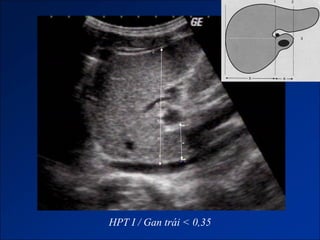

HPT I / Gan trái < 0,35

HPT I / Gan phải > 0,65

Hình ảnh trênCLVT - Giai đoạn sớm: + Gan to. + Tăng tỷ trọng do xơ hóa. - Giai đoạn muộn: + Gan biến đổi hình thái và đường bờ. + Dấu hiệu tăng ALTMC. + Dấu hiệu khác: Dịch ascite – Lách to – Dày thành TM. Nốt tân tạo. Biến chứng (HCC).

HPT I /Gan trái < 0,35

HPT I /Gan phải > 0,65